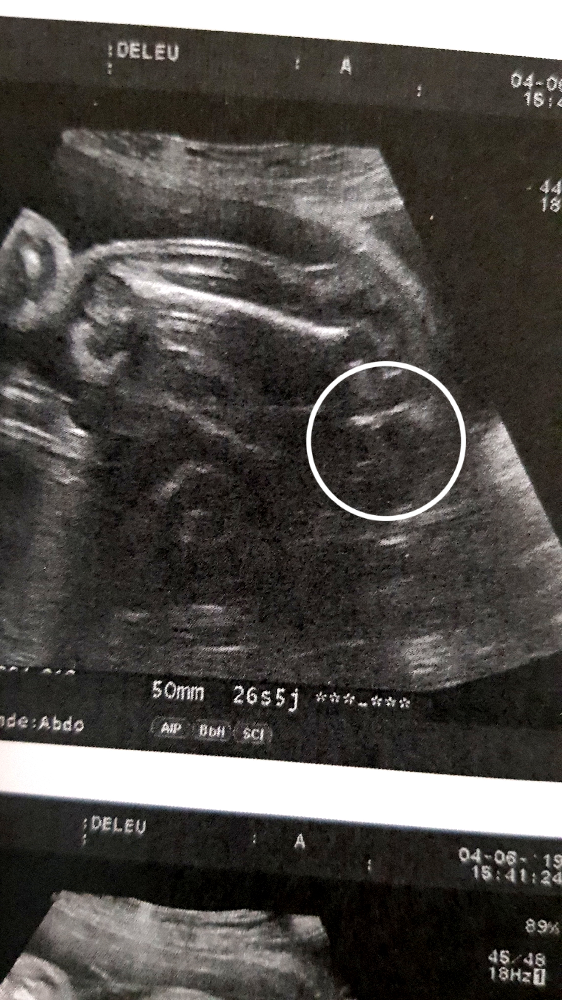

En cette 26ème semaine de grossesse, la taille du bébé de 28 SA est de 33 cm et son poids de 870 g D'ici à la naissance, il va multiplier son poids par trois3 nov 09 à 14 Bonjour Maéva, Ecoute moi je sui a 26 sa 5j et il m'on fait une echo hier et du coup il trouve que mon bb est encore trop petit 600gr, il devrait faire entre 900gr et 1kg donc j'ai fait une amniosynthese hier et je minquiète vraiment des résultatsPendant la SA 26, le bébé mesure entre 34 et 36 centimètres des pieds à la tête et pèse environ 800 grammes Les bébés prématurés nés pendant cette semaine bénéficient d'une prise de

Le bébé à la SA 26 À la semaine 26 d'aménorrhée le bébé mesure entre 34 et 36 centimètres des pieds à la tête et pèse déjà environ 900 grammes Il peut encore bouger avec assez d'agilité dans le ventre maternel, et parfois il peut même étirer complètement son corpsAussi grand qu'une poupée Corolle® Votre futur bébé fait désormais 33 cm, soit la taille d'une poupée Les Chéries de chez Corolle® Incroyable non ? Bébé in utero semaine 26 (28 SA) jours et votre bébé sera là Où en estil en cette 26e semaine de grossesse ?

26 SA / 24 SG 30 cm 650 g 27 SA / 25 SG 32 cm 750 g 28 SA / 26 SG 33 cm 870 g Septième mois de grossesse (29 SA 32 SA) mon bébé a sa peser 408g pour 24 cm les statistiques de ce que tu as marquer ne sont pas a prendre pour tout le monde chaque gossesse est differente !!!!! La 26ème semaine de grossesse correspond à 28 SA du 6ème mois de grossesse Que va t'il se passer pour vous et bébé durant cette semaine ?Poids bébé a 26 sa coucou les filles je sors de chez ma gygy qui m'a annoncé le poids de mon bebe a 26 sa 3 elle pèse 1027 kg !